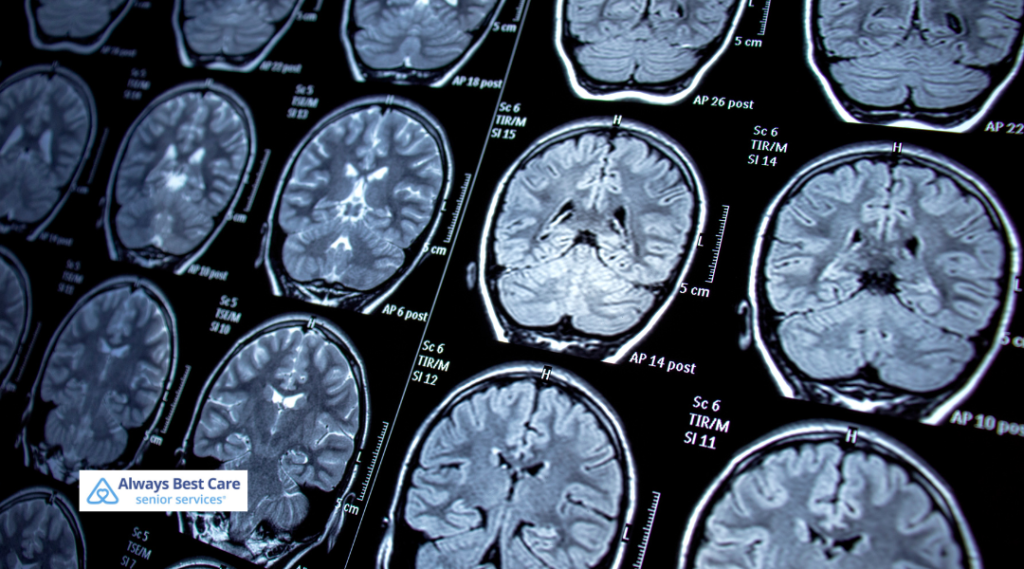

Epilepsy is a neurological condition that causes recurring seizures due to sudden bursts of electrical activity in the brain. These seizures vary in type and intensity — some may cause brief moments of blank stares, while others can lead to full-body convulsions.